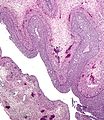

Its cells develop from the follicular cells surrounding the ovarian follicle.[5] The follicular theca cells luteinize into small luteal cells (thecal-lutein cells) and follicular granulosa cells luteinize into large luteal cells (granulosal-lutein cells) forming the corpus luteum. Progesterone is synthesized from cholesterol by both the large and small luteal cells upon luteal maturation. Cholesterol-LDL complexes bind to receptors on the plasma membrane of luteal cells and are internalized. Cholesterol is released and stored within the cell as cholesterol ester. LDL is recycled for further cholesterol transport. Large luteal cells produce more progesterone due to uninhibited/basal levels of protein kinase A (PKA) activity within the cell. Small luteal cells have LH receptors that regulate PKA activity within the cell. PKA actively phosphorylates steroidogenic acute regulatory protein (StAR) and translocator protein to transport cholesterol from the outer mitochondrial membrane to the inner mitochondrial membrane.[6]

Like the previous theca cells, the theca lutein cells lack the aromatase enzyme that is necessary to produce estrogen, so they can only perform steroidogenesis until formation of androgens. The granulosa lutein cells do have aromatase, and use it to produce estrogens, using the androgens previously synthesized by the theca lutein cells, as the granulosa lutein cells in themselves do not have the 17α-hydroxylase or 17,20 lyase to produce androgens.[5] Once the corpus luteum regresses the remnant is known as corpus albicans.[12]